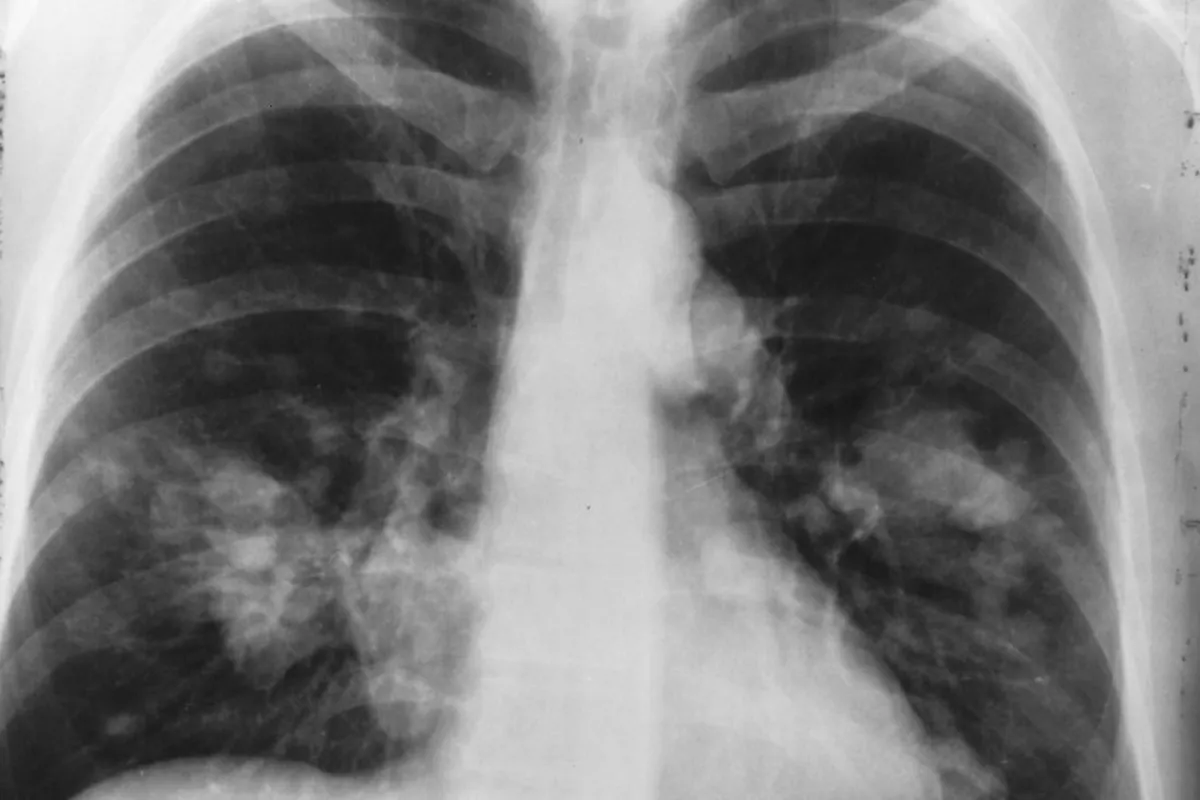

سرطان ریه یکی از رایج‌ترین سرطان‌ها در دنیاست بنابراین باید برای تشخیص و درمان سریع، علائم اولیه را بشناسید. یکی از علائم هشدار این بیماری روی صورت است.

سرطان ریه دومین سرطان رایج در بینِ مردان و زنان است و علت اصلی مرگ و میر در سر تا سر جهان می‌باشد. هر سال ۲۳۰ هزار نفر مبتلا به این بیماری تشخیص داده می‌شوند و در معرض خطر قرار می‌گیرند. البته متخصصان گفته اند که تشخیص اولیه تاثیر زیادی روی احتمال زنده ماندن فرد بر اثر این سرطان دارد؛ بنابراین بسیار مهم است که علائم را بشناسیم. مشخصا یک علامت وجود دارد که روی صورت تاثیر می‌گذارد و اگر متوجه آن شدید، فورا آزمایش سرطان بدهید.

زمانی ورم صورت اتفاق می‌افتد که مایعات در بافت صورت تجمع پیدا می‌کنند و باعث التهاب و پف صورت می‌شوند؛ البته شاید علت‌های غیر سرطانی داشته باشد، اما گاهی اوقات علامت سرطان ریه است. علت هم این است؛ تومور‌هایی که داخل بدن ایجاد شده اند، جریان خون را در یک رگ مهم در قسمت بالای بدن مسدود می‌کنند که این رگ‌ها مسئول انتقال خون از سر به قسمت بالای قفسه سینه، گردن، دست و قلب می‌باشند.

هنگامی که این رگ مسدود می‌شود، وضعیت خطرناک خواهد شد. طبق مطالعات سال ۲۰۱۸ در چنین حالتی سندروم ورید اجوف فوقانی به وجود می‌آید که علت ایجاد این سندروم هم می‌تواند سرطان باشد. علائم این سندرم ممکن است که خودش را در مسدود کردن بخشی از رگ یا کل رگ نشان دهد.

اگر این وضعیت در کل بدن پخش شود، ممکن است به خاطر سرطان‌های دیگر باشد. سرطان ریه رایج‌ترین علت این سندروم است، اما انواع دیگر سرطان‌ها هم در صورتی که در قسمت دیگر بدن پخش شوند، می‌توانند عامل ایجاد این اتفاق باشند.

فضای قفسه سینه بین ریه ها، استخوان سینه و ستون فقرات که شامل قلب و رگ‌های خونی و غدد لنفاوی می‌شود، ممکن است در چنین شرایطی درگیر شوند. تومور ها، سرطان سینه، سرطان تیروئید، سرطان پوست، سرطان خون و دیگر سرطان‌ها هم ممکن است عامل ایجاد چنین وضعیتی باشند.